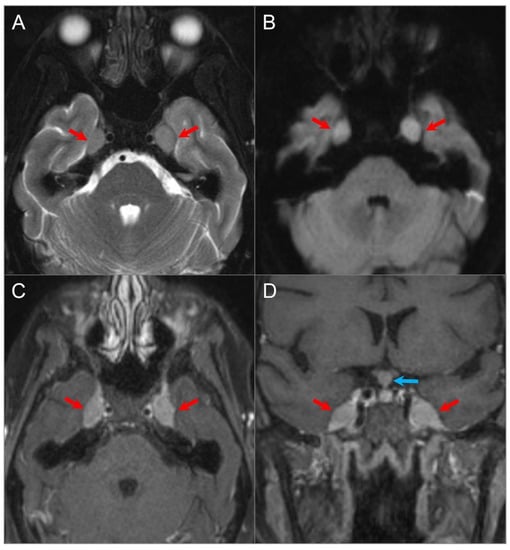

4.1.2. Schwannoma